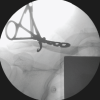

Standard antero-posterior, Grashey and lateral view radiographs were taken both pre- and post-operatively. A pre-operative computed tomography (CT) scan with 3D reconstruction was obtained in all patients for accurate assessment of fracture configuration and measurements of parameters of displacement. The orthopedic trauma association/arbeitsgemeinschaft fur osteosynthesefragen classification system was used to classify both clavicle and scapula. Patients eligible for the study were skeletally mature patients >18 years of age, fresh (injuries within 14 days of presentation) double disruption of the SSSC which met the criteria for significant displacement. Exclusion criteria included minimally displaced floating shoulder, associated neurovascular injury, previously operated shoulder, previous malunion and/or nonunion. Operative indications for ipsilateral fractures comprised of GPA <20°, medialization of >25 mm, open fractures, clavicular shortening of >20 mm or displacement >10 mm with no cortical contact/comminution. Distances and angles were calculated using picture archiving and communication system or by manual methods using protractors. The GPA is measured on 3D CT reconstruction by the angle created by two lines- line 1 extending from the superior glenoid pole to inferior glenoid pole and line 2 connecting the superior glenoid pole to the inferior most pole of inferior pole of scapula. Medialization/lateralization displacement is measured similarly by determining the distance between the vertical planes drawn at the lateral most edge of both scapular fragments (Fig. 1). All patients were operated in floppy lateral decubitus with shoulder girdle and the whole upper limb prepared and draped. Clavicle fracture was fixed first in all cases with an anatomical 3.5 mm clavicle plate using standard direct approach. Brodsky’s direct lateral column approach was taken to fix the scapula which utilizes the plane between infraspinatus and teres minor. 3.5 reconstruction plates, molded to match anatomy, were used for fixing the lateral pillar. Reduction and fixation of clavicle first allows for ease of reduction of the scapular segment; both fixations were carried out in the same seating (Fig. 2 and 3). The shoulder was kept in a universal shoulder immobilizer for up to one week depending upon the associated injuries, following which gentle pendulum exercises with passive movements for the shoulder girdle were initiated. Full range of movements compatible with activities of daily living was started at 2 months. Patients were evaluated clinically with Herscovici and American shoulder and Elbow score (ASES) scoring system and imaged at regular intervals of 2, 6 and 12 weeks in AP, lateral, Grashey views. Additional follow-up for any complication including but not limited to plate prominence, poor range of motion, persistent pain for a period of 18 months (Fig. 4).